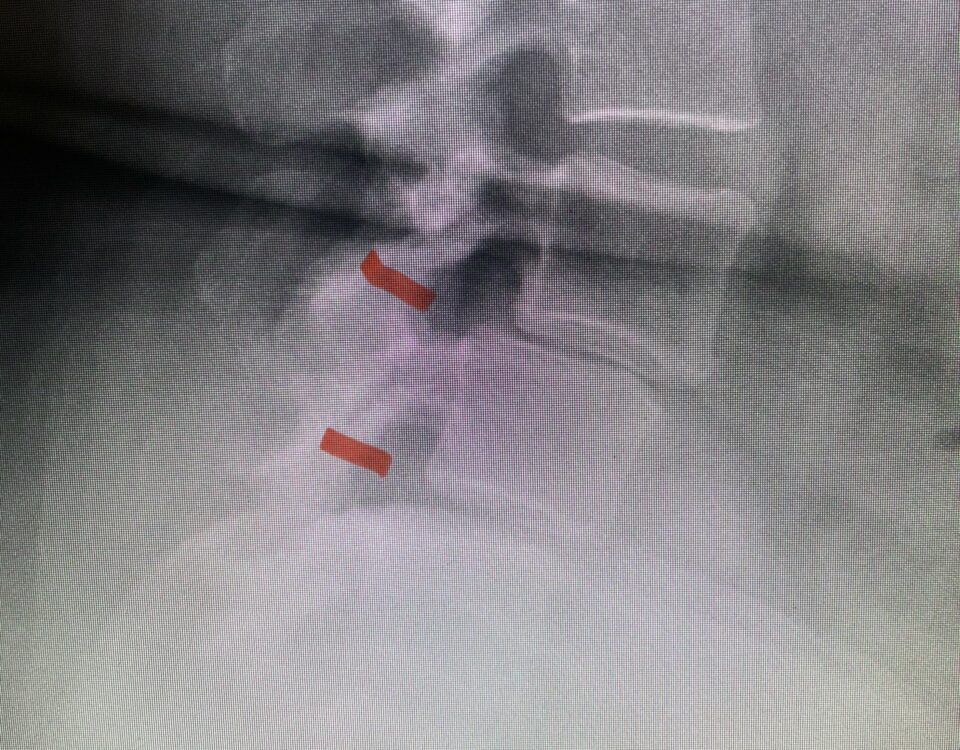

Here is a tough case: This is a 72 year-old male who presented with several months of progressive neck pain without symptoms of the arms or legs. […]